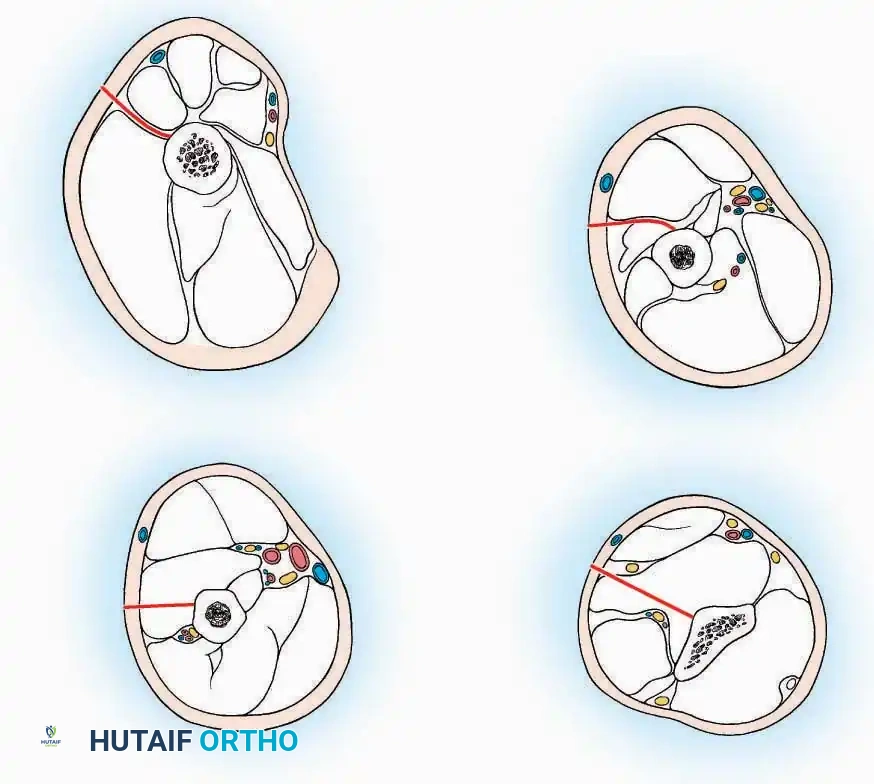

Anterolateral Approach

The anterolateral approach is widely considered the "universal incision" for the foot and ankle. It provides unparalleled access to the ankle joint, the talus, and the majority of the tarsal articulations, while safely avoiding the major anterior neurovascular bundle. The only tarsal joints inaccessible via this route are the naviculocuneiform joints (specifically the medial and intermediate).

Indications: Total talectomy, triple arthrodesis, ankle arthrodesis, and open reduction of complex talar neck fractures.

Surgical Technique:

* Incision: Begin over the anterolateral aspect of the leg, medial to the fibula and 5 cm proximal to the ankle joint line. Carry it distally over the joint, crossing the anterolateral aspect of the talar body and the calcaneocuboid joint, terminating at the base of the fourth metatarsal.

* Superficial Dissection: Incise the superficial fascia and the superior and inferior extensor retinacula down to the periosteum of the tibia and the ankle joint capsule.

* Vascular Ligation: This trajectory usually requires the identification and ligation of the anterolateral malleolar and lateral tarsal arteries.

* Nerve Protection: Retract the skin edges carefully. Identify and protect the intermediate dorsal cutaneous branches of the superficial peroneal nerve (SPN), which frequently cross the distal aspect of this incision.

* Muscle Management: Identify the origin of the extensor digitorum brevis (EDB) muscle on the lateral calcaneus. Divide it in the direction of its fibers, or detach its origin entirely and reflect it distally to expose the subtalar and calcaneocuboid joints.

* Deep Exposure: Retract the extensor digitorum longus (EDL) tendons, the dorsalis pedis artery, and the deep peroneal nerve (DPN) medially. Incise the anterior ankle capsule to expose the tibiotalar joint.

* Tarsal Exposure: Expose the talonavicular joint by dissecting deep to the extensor tendons and incising its capsule transversely. Continue laterally through the capsule of the calcaneocuboid joint. By excising the fat pad within the sinus tarsi (lateral and inferior to the talar neck), the posterior facet of the subtalar joint is brought into direct view.

Anterior Approach

Indications: Total ankle arthroplasty (TAA), anterior ankle arthrodesis, and excision of anterior tibial/talar osteophytes (anterior impingement).

Surgical Technique:

* Incision: Make a 10 to 15 cm longitudinal incision over the anterior aspect of the ankle, centered exactly midway between the medial and lateral malleoli.

* Superficial Dissection: Incise the superficial fascia. Identify and protect the superficial peroneal nerve branches laterally and the saphenous nerve medially.

* Internervous Plane: The deep dissection exploits the plane between the Extensor Hallucis Longus (EHL) tendon (innervated by the deep peroneal nerve) and the Extensor Digitorum Longus (EDL) tendons (also innervated by the deep peroneal nerve).

* Neurovascular Bundle: Incise the extensor retinaculum. Carefully identify the anterior tibial artery and the deep peroneal nerve, which typically lie between the EHL and EDL, or directly deep to the EHL. Retract the neurovascular bundle laterally with the EDL, or medially with the EHL, depending on the specific anatomical variant encountered (lateral retraction is most common).

* Capsulotomy: Incise the anterior joint capsule longitudinally. Elevate the capsule subperiosteally from the anterior tibia and the talar neck to expose the entire tibiotalar articulation.